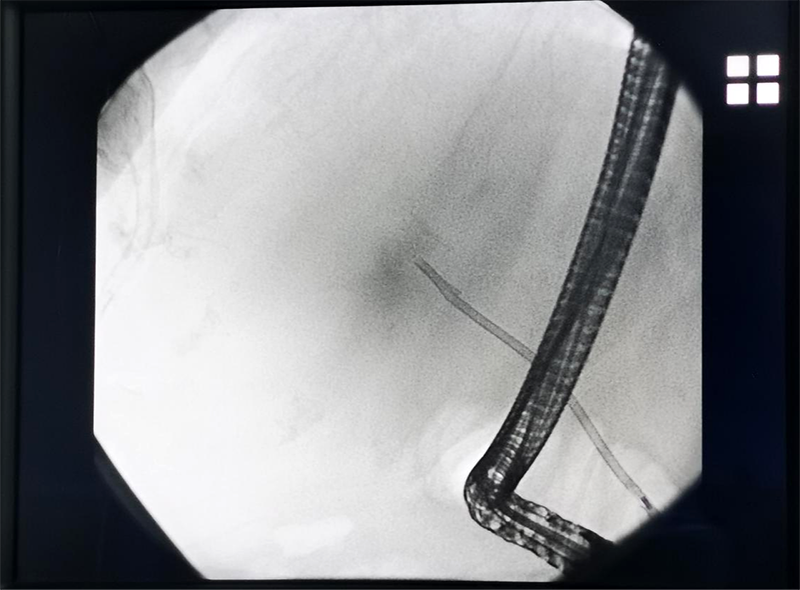

日前,内镜中心刘小玉主任医师率领团队为一耄耋老人成功完成了内镜逆行胰胆管造影术(ERCP)+胆管支架置入术,解除胆道梗阻,让患者转危为安。

经充分准备,刘小玉主任医师率领医护团队为患者进行手术,终顺利置入胆管支架,整台手术仅耗时约20分钟。术后,患者现无腹痛、发热,黄疸逐渐减轻,日常生活基本恢复。

刘小玉主任医师介绍,ERCP技术是诊断胆管、胰管病变的金标准。随着技术的发展,它已从单纯的诊断性技术发展为以治疗为主的综合性技术,在成人治疗胆胰疾病方面应用非常广泛。主要适应症为胆管结石、肿瘤、炎症、寄生虫、不明原因的阻塞性黄疸等疾病,并具有创伤小、痛苦少、费用低、恢复快及可重复操作等优势,可成为治疗胆胰疾病的首选诊疗方法。

ERCP是经内镜逆行性胰胆管造影术,是指将纤维十二指肠镜经口插至十二指肠降部,经十二指肠乳头导入专用器械进入胆管或者胰管内,在X线透视下注射造影剂造影,通过球囊取石、支架植入、脱落细胞/组织收集等操作,完成对胆、胰疾病的诊断,并在诊断基础之上实施相应介入治疗技术的总称。经过近半个世纪的技术进步,ERCP技术已从一种诊断手段发展成为了集疾病诊断和微创治疗为一体的综合技术。在ERCP的基础上,可以进行十二指肠乳头括约肌切开术(EST)、胆道结石取出术、内镜下鼻胆汁引流术(ENBD)、内镜下胆汁内引流术(ERBD)等介入治疗。十二指肠乳头仅有米粒大小,在内镜下很难找到,加上胆总管又短又细,非常考验专家能力,ERCP是操作难度高的内镜手术,被誉为内镜技术“皇冠上的明珠”。